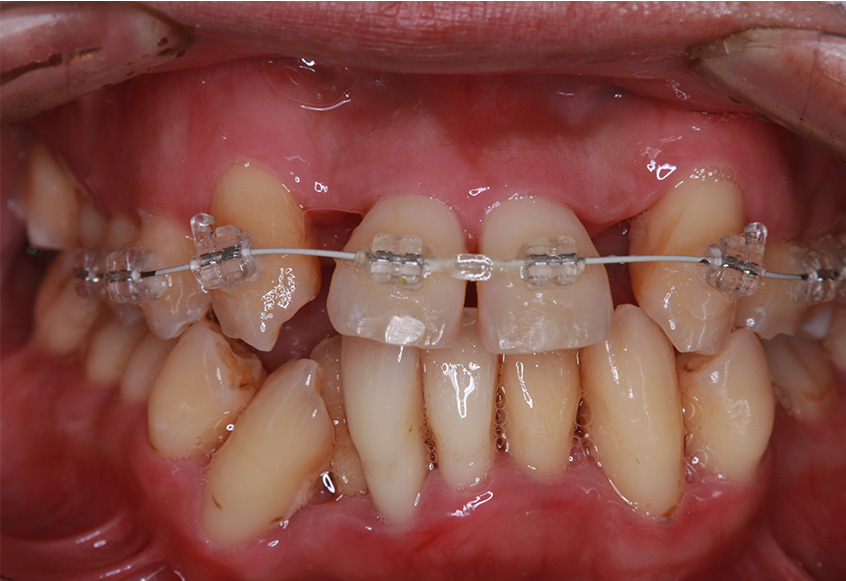

最初のお口の中 ワイヤー装着して治療を開始

-